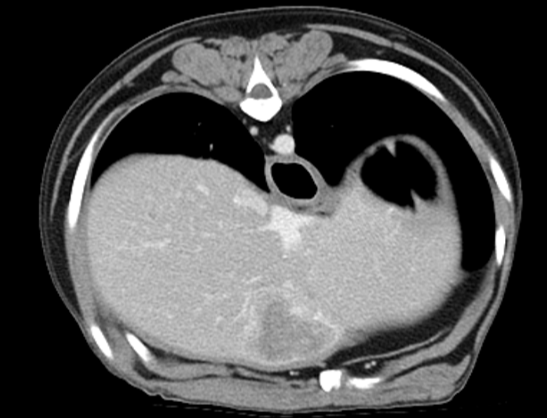

160ch CT

160 slice CT는 빠른 속도로 환자의 마취 시간을 줄이며(5분 이내) 정확한 진단에 도움을 줍니다. 또한 심장 등의 장기를 평가함에 있어 기존 64채널 CT에 비해

우수한 해상도의 영상을 획득 가능합니다.

160 slice CT는 국내 동물병원에서 최상급 촬영장비(Toshiba Acquilion Prime)에 해당하며 conventional CT 촬영 이외에도 추가적인 body perfusion,

dual energy 등도 가능합니다.

160채널 CT는 고화질 영상으로 숨어있는 비정상적인 문제점들을 찾아내어 진단 및 치료에 도움을 주고 있습니다.

3D 재구성을 통해 외과의에게 더욱 정확한 정보를 제공할 수 있어 수술의 위험성을 감소시킵니다.

3kg cardiac CT 3D recon

4kg abdominal aorta 3D recon

02흉부 CT

· 심장의 종양 및 혈관기형(PDA 등) 평가

· 폐의 실질 변화 및 종양, 전이 평가

· 종격동 및 기관지, 식도 평가